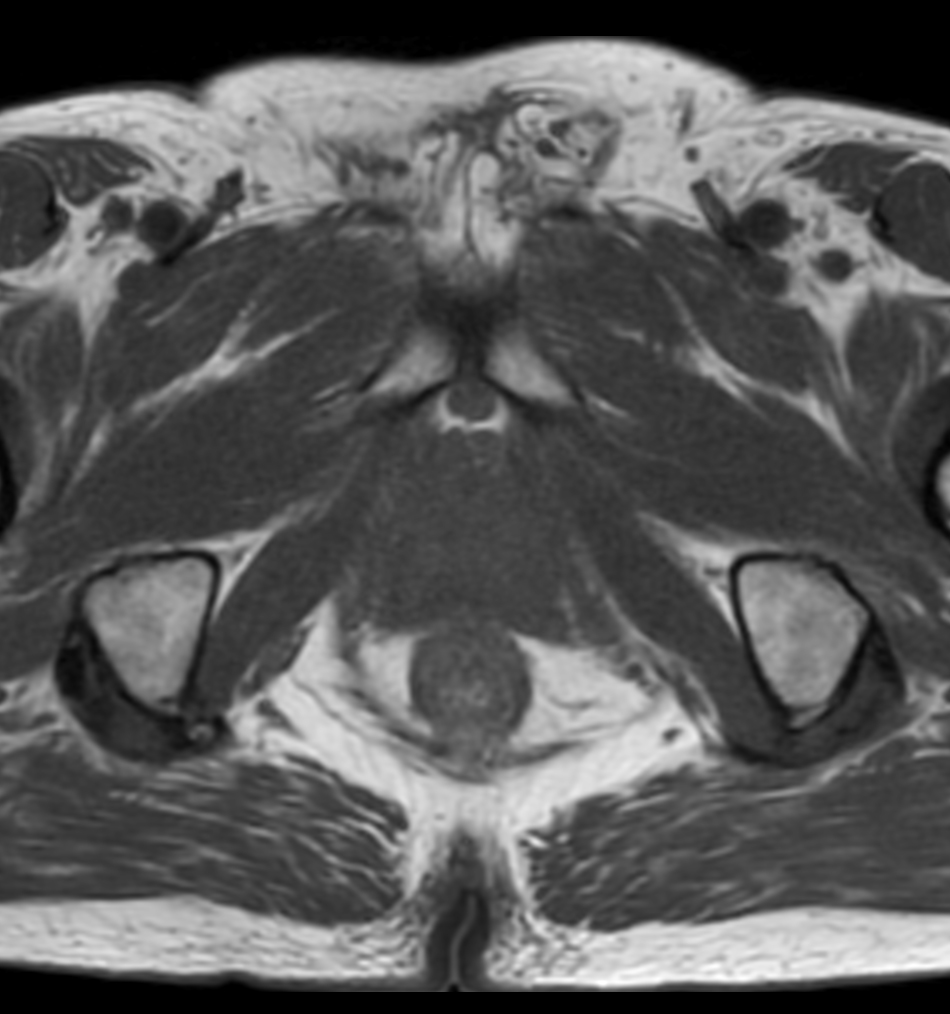

Prostate lesion with fat-free mDIXON XD imaging

Seirei Mikatahara General Hospital, Japan